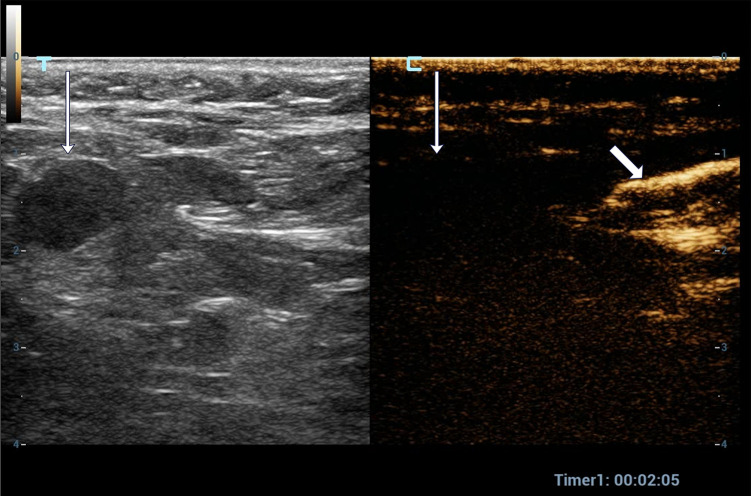

Methods: A total of 176 patients with breast cancer who underwent preoperative SLN-CEUS to trace axillary sentinel lymph nodes were included. The positive result of SLN-CEUS was defined as both lymphatic vessels and SLN visible. The negative result was defined as the visible lymphatic vessels but the SLNs invisible, and neither lymphatic vessel nor SLNs invisible. Clinical features, histopathology, ultrasound features and doses of contrast agents were analyzed between the positive and negative groups.

Abstract Image